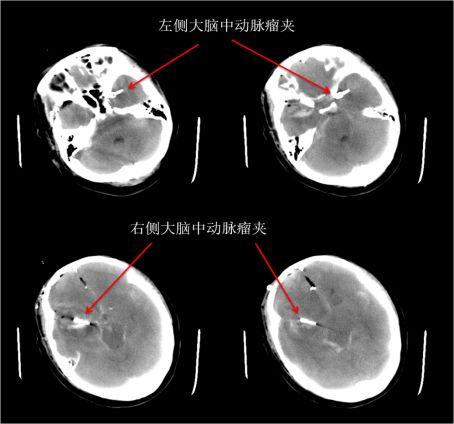

头部CT提示右侧颞叶血肿、蛛网膜下腔出血

患者术后8小时复查CT